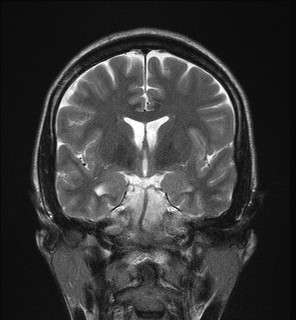

Hippocampal sclerosis (HS) is a neuropathological condition with severe neuronal cell loss and gliosis in the hippocampus, specifically in the CA-1 (Cornu Ammonis area 1) and subiculum of the hippocampus. It was first described in 1880 by Wilhelm Sommer.[1] Hippocampal sclerosis is a frequent pathologic finding in community-based dementia. Hippocampal sclerosis can be detected with autopsy or MRI. Individuals with hippocampal sclerosis have similar initial symptoms and rates of dementia progression to those with Alzheimer's disease (AD) and therefore are frequently misclassified as having Alzheimer's Disease. But clinical and pathologic findings suggest that hippocampal sclerosis has characteristics of a progressive disorder although the underlying cause remains elusive.[2] A diagnosis of hippocampal sclerosis has a significant effect on the life of patients because of the notable mortality, morbidity and social impact related to epilepsy, as well as side effects associated with antiepileptic treatments.[3]

Mesial temporal sclerosis is a specific pattern of hippocampal neuron cell loss.[4][5] There are 3 specific patterns of cell loss. Cell loss might involve sectors CA1 and CA4, CA4 alone, or CA1 to CA4.[5] Associated hippocampal atrophy and gliosis is common.[4] MRI scan commonly displays increased T2 signal and hippocampal atrophy.[4] Mesial temporal sclerosis might occur with other temporal lobe abnormalities (dual pathology).[4] Mesial temporal sclerosis is the most common pathological abnormality in temporal lobe epilepsy.[4][5] It has been linked to abnormalities in TDP-43.[6]